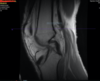

Clinically I was concerned about the integrity of the ACL so we ordered an MRI the radiologist interpreted normal and intact

Radiology report noted an intact ACL and lateral meniscal tear with extrusion.

My interpretation of the ACL I was concerned about his loss of overall integrity especially given the bone bruising in the proximal tibia.

I also was able to better interpret the tunnel placement as well as absence of any tunnel osteolysis.